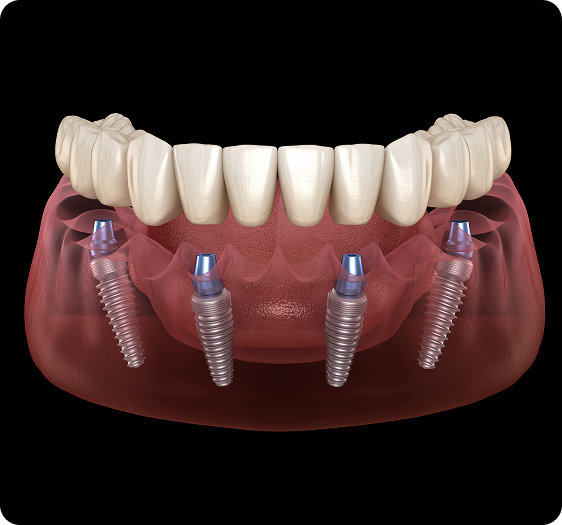

All-on-4®

The All-on-4 ® concept refers to a procedure where four or more implants are utilised to support a full set of teeth within days. This treatment concept requires thorough planning and can be a great alternative to dentures. The All-on-4 ® technique reduces the need for bone grafting, which can make the overall procedure faster, require less healing time and more affordable for patients.

The All-on-4® procedure is a dental implant solution designed to replace an entire arch of missing teeth, offering greater bite force compared to traditional dentures.

This treatment may be suitable for individuals with multiple missing teeth, advanced gum disease, severe tooth decay, or those unable to restore their teeth through other methods.

All-on-4® works by securing a full set of durable, artificial teeth onto four strategically placed implants—two positioned at the front and two at the back of the jawbone. This approach ensures stability while being less invasive than some conventional full-mouth restoration techniques.